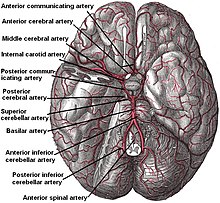

Small arteries beneath brain.

According to Koffler et al., lacunes are derived from an "occlusion of a single deep penetrating artery that arises directly from the constituents of the circle of Willis, cerebellar arteries, and basilar artery". Other lesions that are associated with lacunes appear in the "deep nuclei of the brain (37% putamen, 14% thalamus, and 10% caudate) as well as the pons (16%) or the posterior limb of the internal capsule (10%)". These lesions are less common within other brain regions such as the cerebellum, cerebral white matter and anterior limb of the internal capsule.[9]

The two proposed mechanisms are microatheroma and lipohyalinosis.[10] At the beginning, lipohyalinosis was thought to be the main small vessel pathology, but microatheroma now is thought to be the most common mechanism of arterial occlusion (or stenosis). Occasionally, atheroma in the parent artery blocks the orifice of the penetrating artery (luminal atheroma), or atheroma involves the origin of the penetrating artery (junctional atheroma). Alternatively, hypoperfusion is believed to be the mechanism when there is stenosis of the penetrating artery. When no evidence of small vessel disease is found on histologic examination, an embolic cause is assumed, either artery-to-artery embolism or cardioembolism. In one recent series, 25% of patients with clinical radiologically defined lacunes had a potential cardiac cause for their strokes.